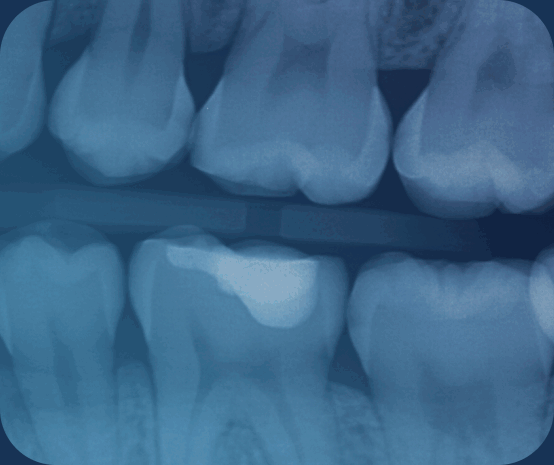

One of our diagnostic tools includes the use of AI technology. Humans see up to 6 shades of grey while reading x-rays. AI sees 600 shades of grey while reading an x-ray, giving our doctors a much more complete view of your oral health.